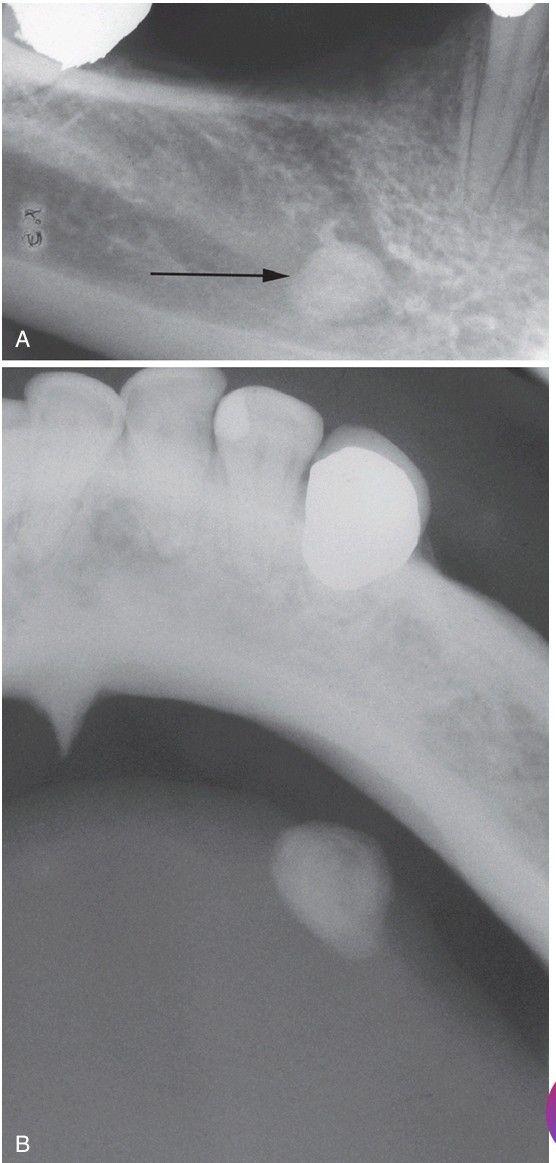

. A, Periapical film showing discrete radiopacity (arrow) superimposed on the body of the mandible. Care must be taken not to confuse such lesions with intrabony pathosis. B, Occlusal radiograph of same patient demonstrating radiopaque stone in Wharton duct.